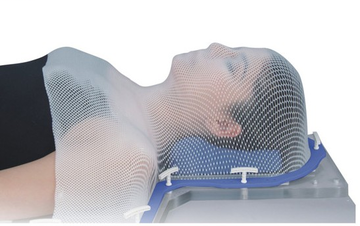

Fabrication des accessoires d’immobilisation (au besoin)

Le traitement se doit d’être très précis. Afin de s’assurer de sa précision, il sera peut-être nécessaire de vous fabriquer un accessoire d’immobilisation dans lequel vous serez installé à chaque traitement.

Le type d’accessoire varie en fonction de la région traitée. Si, lors de sa fabrication, vous avez une douleur causée par le positionnement, veuillez en aviser les technologues. Ils feront leur possible pour améliorer votre confort.

Si on ne vous a pas mentionné la fabrication d’un accessoire d’immobilisation, vous n’en aurez pas besoin.